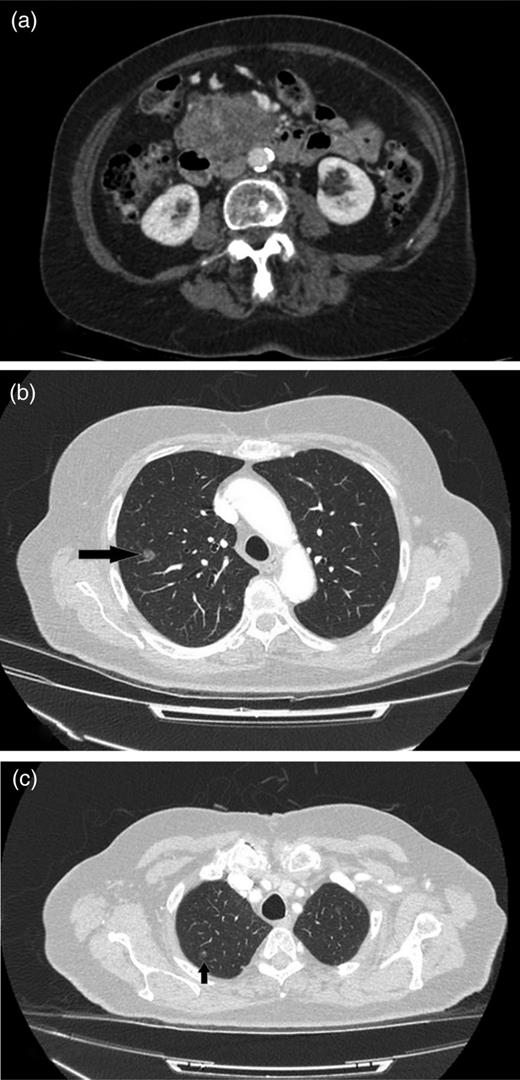

CT shows cystic mass in the uncinate process of pancreas measuring 4 cm in 2008.

(a) CT image of 2015, a mass lesion in the head of the pancreas with solid and cystic components (bunch of grapes appearance). The lesion measures 7.2 × 4.8 cm in the axial dimension and 7.2 cm in the coronal dimension. (b and c) Multiple focal ground-glass density nodules in both upper lobes of the lungs, largest measuring 1 cm in the right upper lobe.